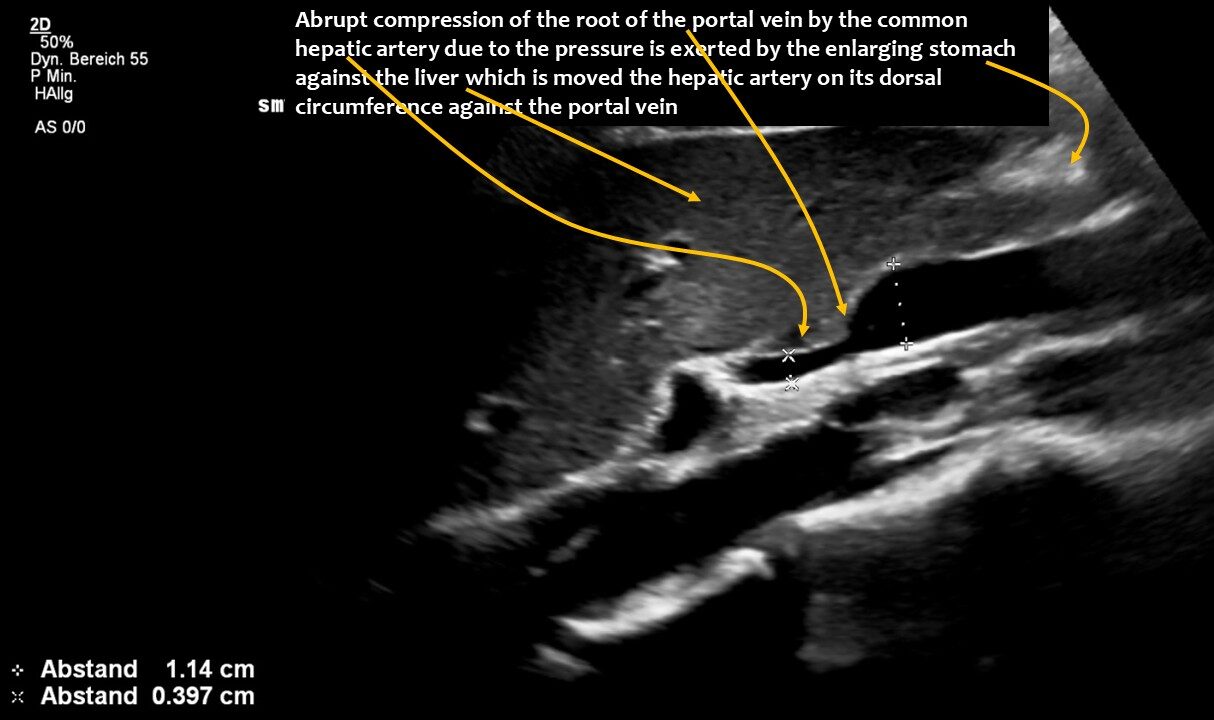

The longitudinal section showing the continuation of the superior mesenteric artery (SMA) into the root of the portal vein reveals an abrupt narrowing of the portal vein, caused by compression from the common hepatic artery.

The enlargement of the superior mesenteric vein was due to compression of the root of the portal vein by the common hepatic artery. This resulted in an increasing outflow obstruction from both the distended superior mesenteric vein and the now curled splenic vein.

The volume of food ingested and the associated enlargement of the stomach now led to a critical situation: the stomach pushed the hepatic artery (arteria hepatica communis), which runs along the underside of the liver, against the portal vein (vena portae), which carries blood from the spleen and intestines to the liver. This compressed the portal vein and caused blood to accumulate in the splenic vein (Vena lienalis/Vena splenica) and, above all, in the superior mesenteric vein. While the splenic vein runs parallel to the pars horizontalis duodeni, the superior mesenteric vein cuts across the duodenum at a right angle, similar to the superior mesenteric artery. The congestion of the superior mesenteric vein led to compression of the duodenum, even though there was sufficient space between the superior mesenteric artery and the duodenum. However, after food intake, the superior mesenteric artery shifted far to the left and thus no longer formed a clamp with the aorta for the duodenum. The swelling of the superior mesenteric vein, which is supplied with significantly more blood after food intake than when fasting in order to transport food components to the liver, was so severe as a result of the compression of the portal vein that food could no longer pass through the pars horizontalis duodeni. The clinical consequences for the patient were increasing nausea after eating due to the considerable distension of the pars descendens duodeni, rapid satiety, impaired food transport from the stomach despite lively peristaltic contractions of the stomach (misinterpreted elsewhere as gastroparesis), vomiting and significant weight loss. Even feeding via a percutaneous jejunal tube and a gastric tube could not stop the weight loss.